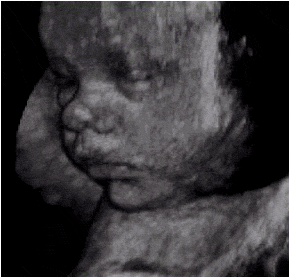

Ecotomografía de un feto de término que muestra los rasgos faciales. Observe el aspecto rechoncho del feto, producto del depósito de grasa subcutanea.